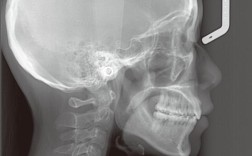

| 头颅侧位片 | 二维影像,包含颅骨、颌骨、牙齿、软组织的侧位轮廓 | 分析颌骨前后位置关系(如凸颌、凹颌)、牙齿倾斜角度、面部软组织形态,制定骨性方案 |

- 头颅侧位片:患者侧立于设备前,耳朵与耳塞贴合,眶点与眶托接触,嘴唇自然闭合,拍摄时保持平静呼吸。

拍片完成后,医生会结合临床检查和影像数据,分析牙齿、颌骨、软组织的关联问题,通过全景片判断牙根长度是否适合移动,头颅侧位片计算骨骼畸形的角度,CBCT设计埋伏牙牵引路径,最终将影像数据与模型、面型照片结合,制定包含拔牙、扩弓、牵引等步骤的个性化矫正方案。